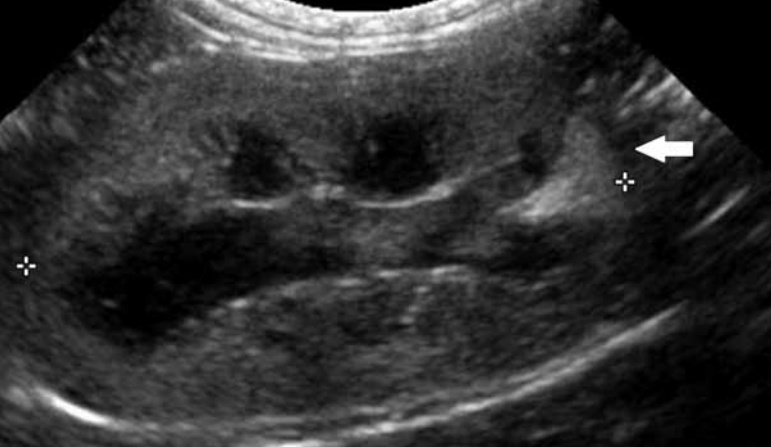

6-2. 신우신염(Pyelonephritis)(그림 13)

신우신염은 세균 감염에 의한 신우 및 신실질 염증입니다.

초음파 영상 소견은 신우에 경미한 확장, 근위 요관의 확장, 무에코 또는 고에코 잔사(debris), 둔화되고 불명확한 신배를 보입니다. 급성 신우신염에서는 신우 및 요관 확장이 없을 수도 있습니다.

신장 크기는 급성에서 정상 또는 증가, 만성에서는 정상 또는 감소를 보이며, 추가 소견으로는 피질의 고에코화, 신장 능선(renal crest)을 따라 고에코 선을 보이고, 피질 또는 수질 내 국소의 고에코 혹은 저에코 병변, 피질–수질 경계 불분명 등이 있습니다. 영상 소견은 매우 다양하며 비특이적입니다.